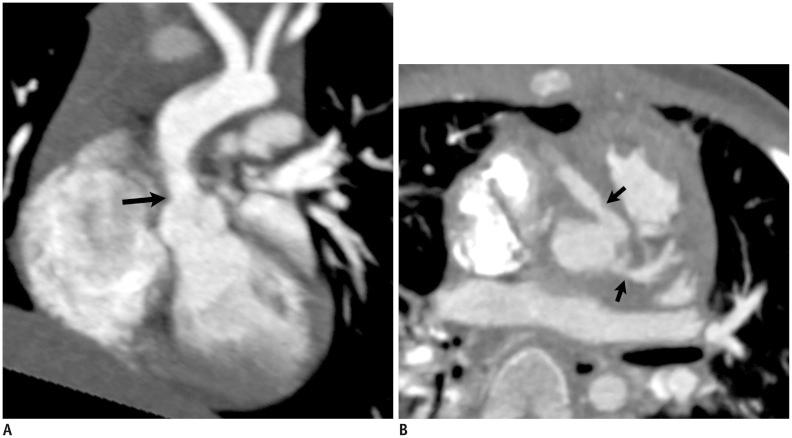

Coronary artery problems in children usually have a significant impact on both short-term and long-term outcomes. Early and accurate diagnosis, therefore, is crucial but technically challenging due to the small size of the coronary artery, high heart rates, and limited cooperation of children. Coronary artery visibility on CT and MRI in children is considerably improved with recent technical advancements. Consequently, CT and MRI are increasingly used for evaluating various congenital and acquired coronary artery abnormalities in children, such as coronary artery anomalies, aberrant coronary artery anatomy specific to congenital heart disease, Kawasaki disease, Williams syndrome, and cardiac allograft vasculopathy.